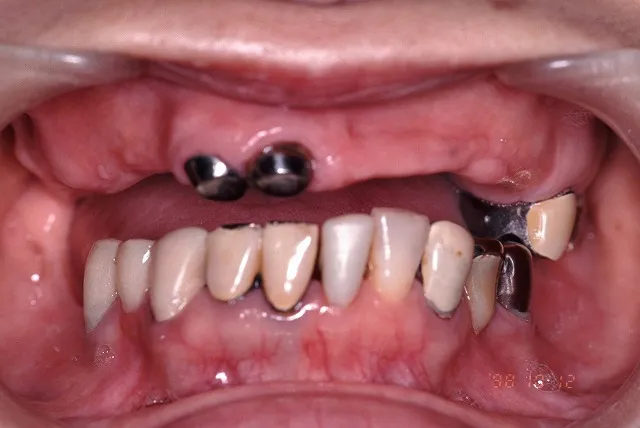

治療前

■治療前